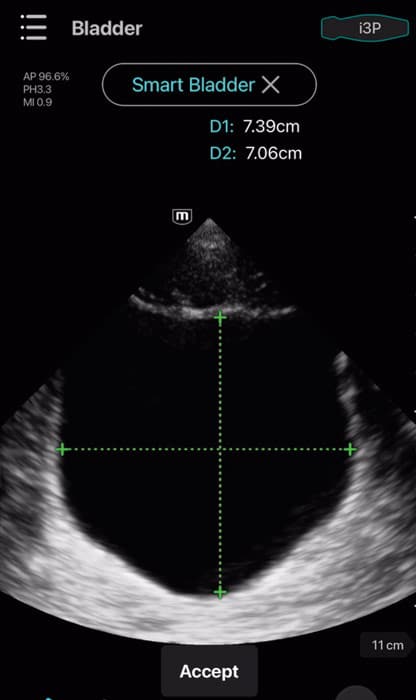

- Scanning modes: B-mode, M-mode, Color Doppler, Power Doppler, PW, and Tissue Doppler Imaging

- Dedicated presets for Cardiac, Abdomen, Lung, Transcranial Imaging (TCI), Emergency Medicine (EM), Trauma (FAST), EM Abdominal

- Aortic Aneurysm (AAA), Bladder, OB/GYN, and Vascular

Clinical Images